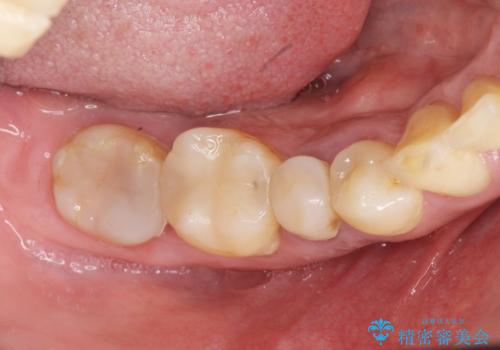

- 88万円(インプラント2本分)費用は治療当時の料金となります

インプラント周囲には骨の増生を埋入時に同時に行っています。